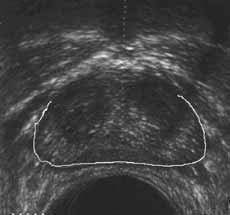

Внутриполостное ультразвуковое исследование в диагностике рака мочевого пузыря и предстательной железы.

Рис. 13 и 14. (Слева) Фиброзно-мышечная строма предстательной железы. (Справа) Капсула предстательной железы.

Новости лучевой диагностики 2001 1-2: 40-46